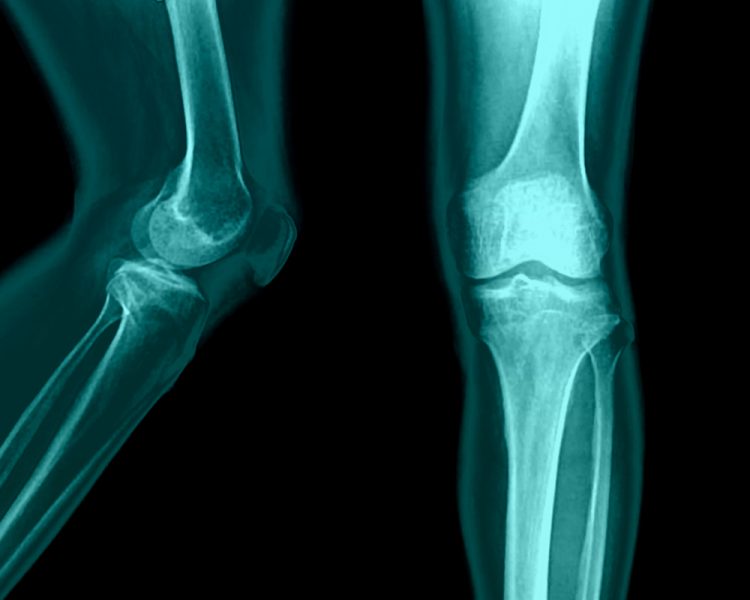

Третман против остеоартритис на вашата чинија

Доколку страдате од остеоартритис (ОА) на колената, имаме некои интересни и добри вести за вас. Исхраната богата со овошје и зеленчук се покажа дека помага да се намали воспалението и болката во зглобовите. Прочитајте за да дознаете како може храната да ви помогне во оваа состојба.

Воспалението произведува слободни радикали, молекулите што ја оштетуваат клетката, кои се формираат како одговор на токсините и природните телесни процеси. Синовијата (перничето помеѓу коленото и зглобот) е склона кон оштетување од слободните радикали како кожата, очите или секое друго ткиво на телото.

Антиоксидансите го штитат телото од слободните радикали. Постарите истражувања од Зборникот на Националната академија на науките и клиничката ревматологија покажаа дека некои антиоксиданти можат да помогнат во спречувањето на артритис, забавување на прогресијата и намалување на болката.